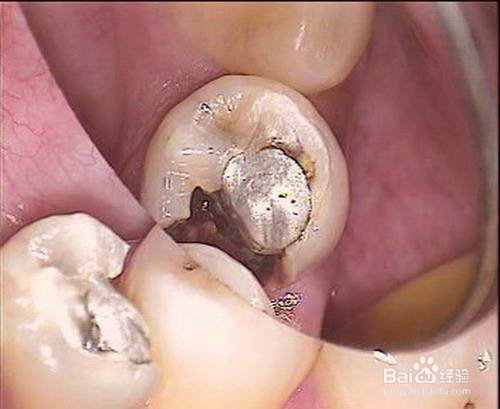

3、怎么判断有没有继发龋?看看牙齿有没有墨迹或者是黑斑,如果牙齿有墨迹、或者黑斑,说明牙齿有继发龋牙的可能,需要进一步检查。

5、怎么判断有没有继发龋?看看牙齿的补充物上有没有腐蚀的情况,如果牙齿的补充物上有腐蚀的情况,而且还比较严重,那就有可能有继发龋牙。

6、怎么判断有没有继发龋?除了以上所说的那几个方面,还可以看看牙齿上有没有黑洞,如果有,也有以上的情况,那就说明有继发龋牙。